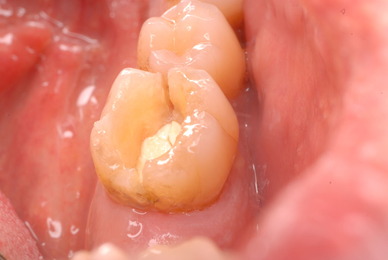

これぞ医師の姿ではないでしょうか。![11229551_834920046584649_8659418848563116234_n[1]](https://livedoor.blogimg.jp/netdental/imgs/c/0/c098deb4.jpg)

![11053897_834920076584646_6691737990508884178_n[1]](https://livedoor.blogimg.jp/netdental/imgs/b/b/bb679b8f.jpg)

![11010956_834920133251307_8897824032330972564_n[1]](https://livedoor.blogimg.jp/netdental/imgs/c/2/c2aa3129.jpg)

![10403096_834920093251311_4823181277198290695_n[1]](https://livedoor.blogimg.jp/netdental/imgs/b/7/b77edc79.jpg)